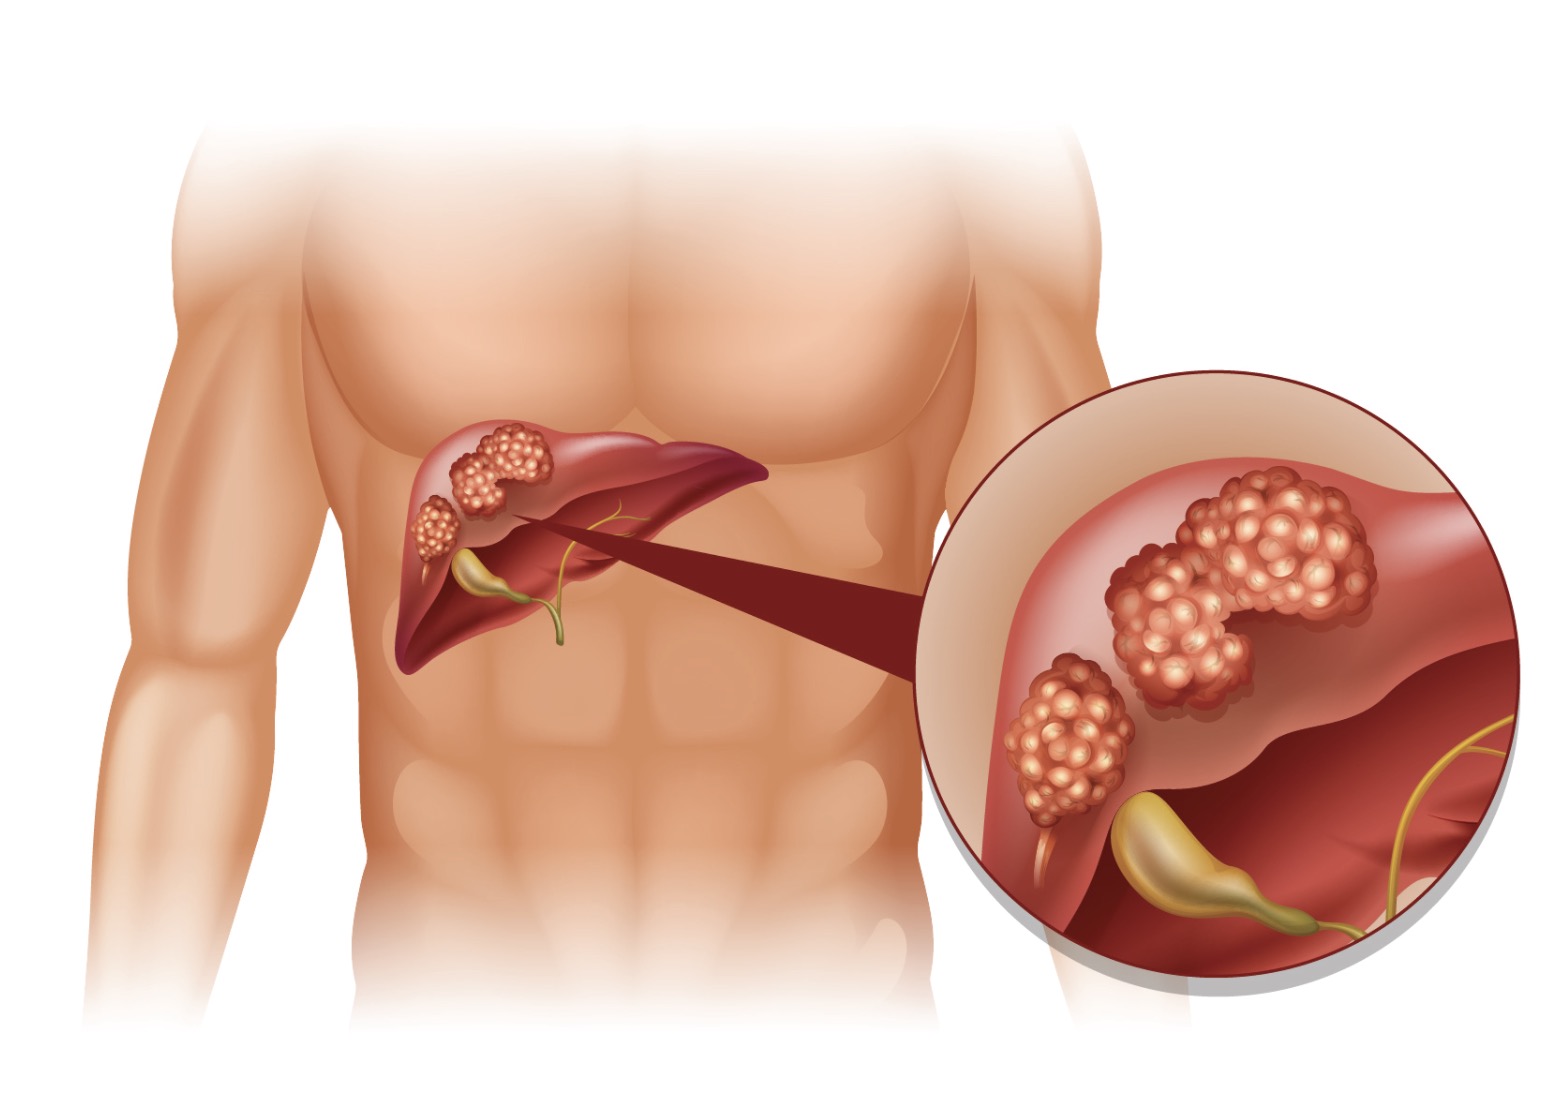

Изображения заболеваний печени: признаки и симптомы